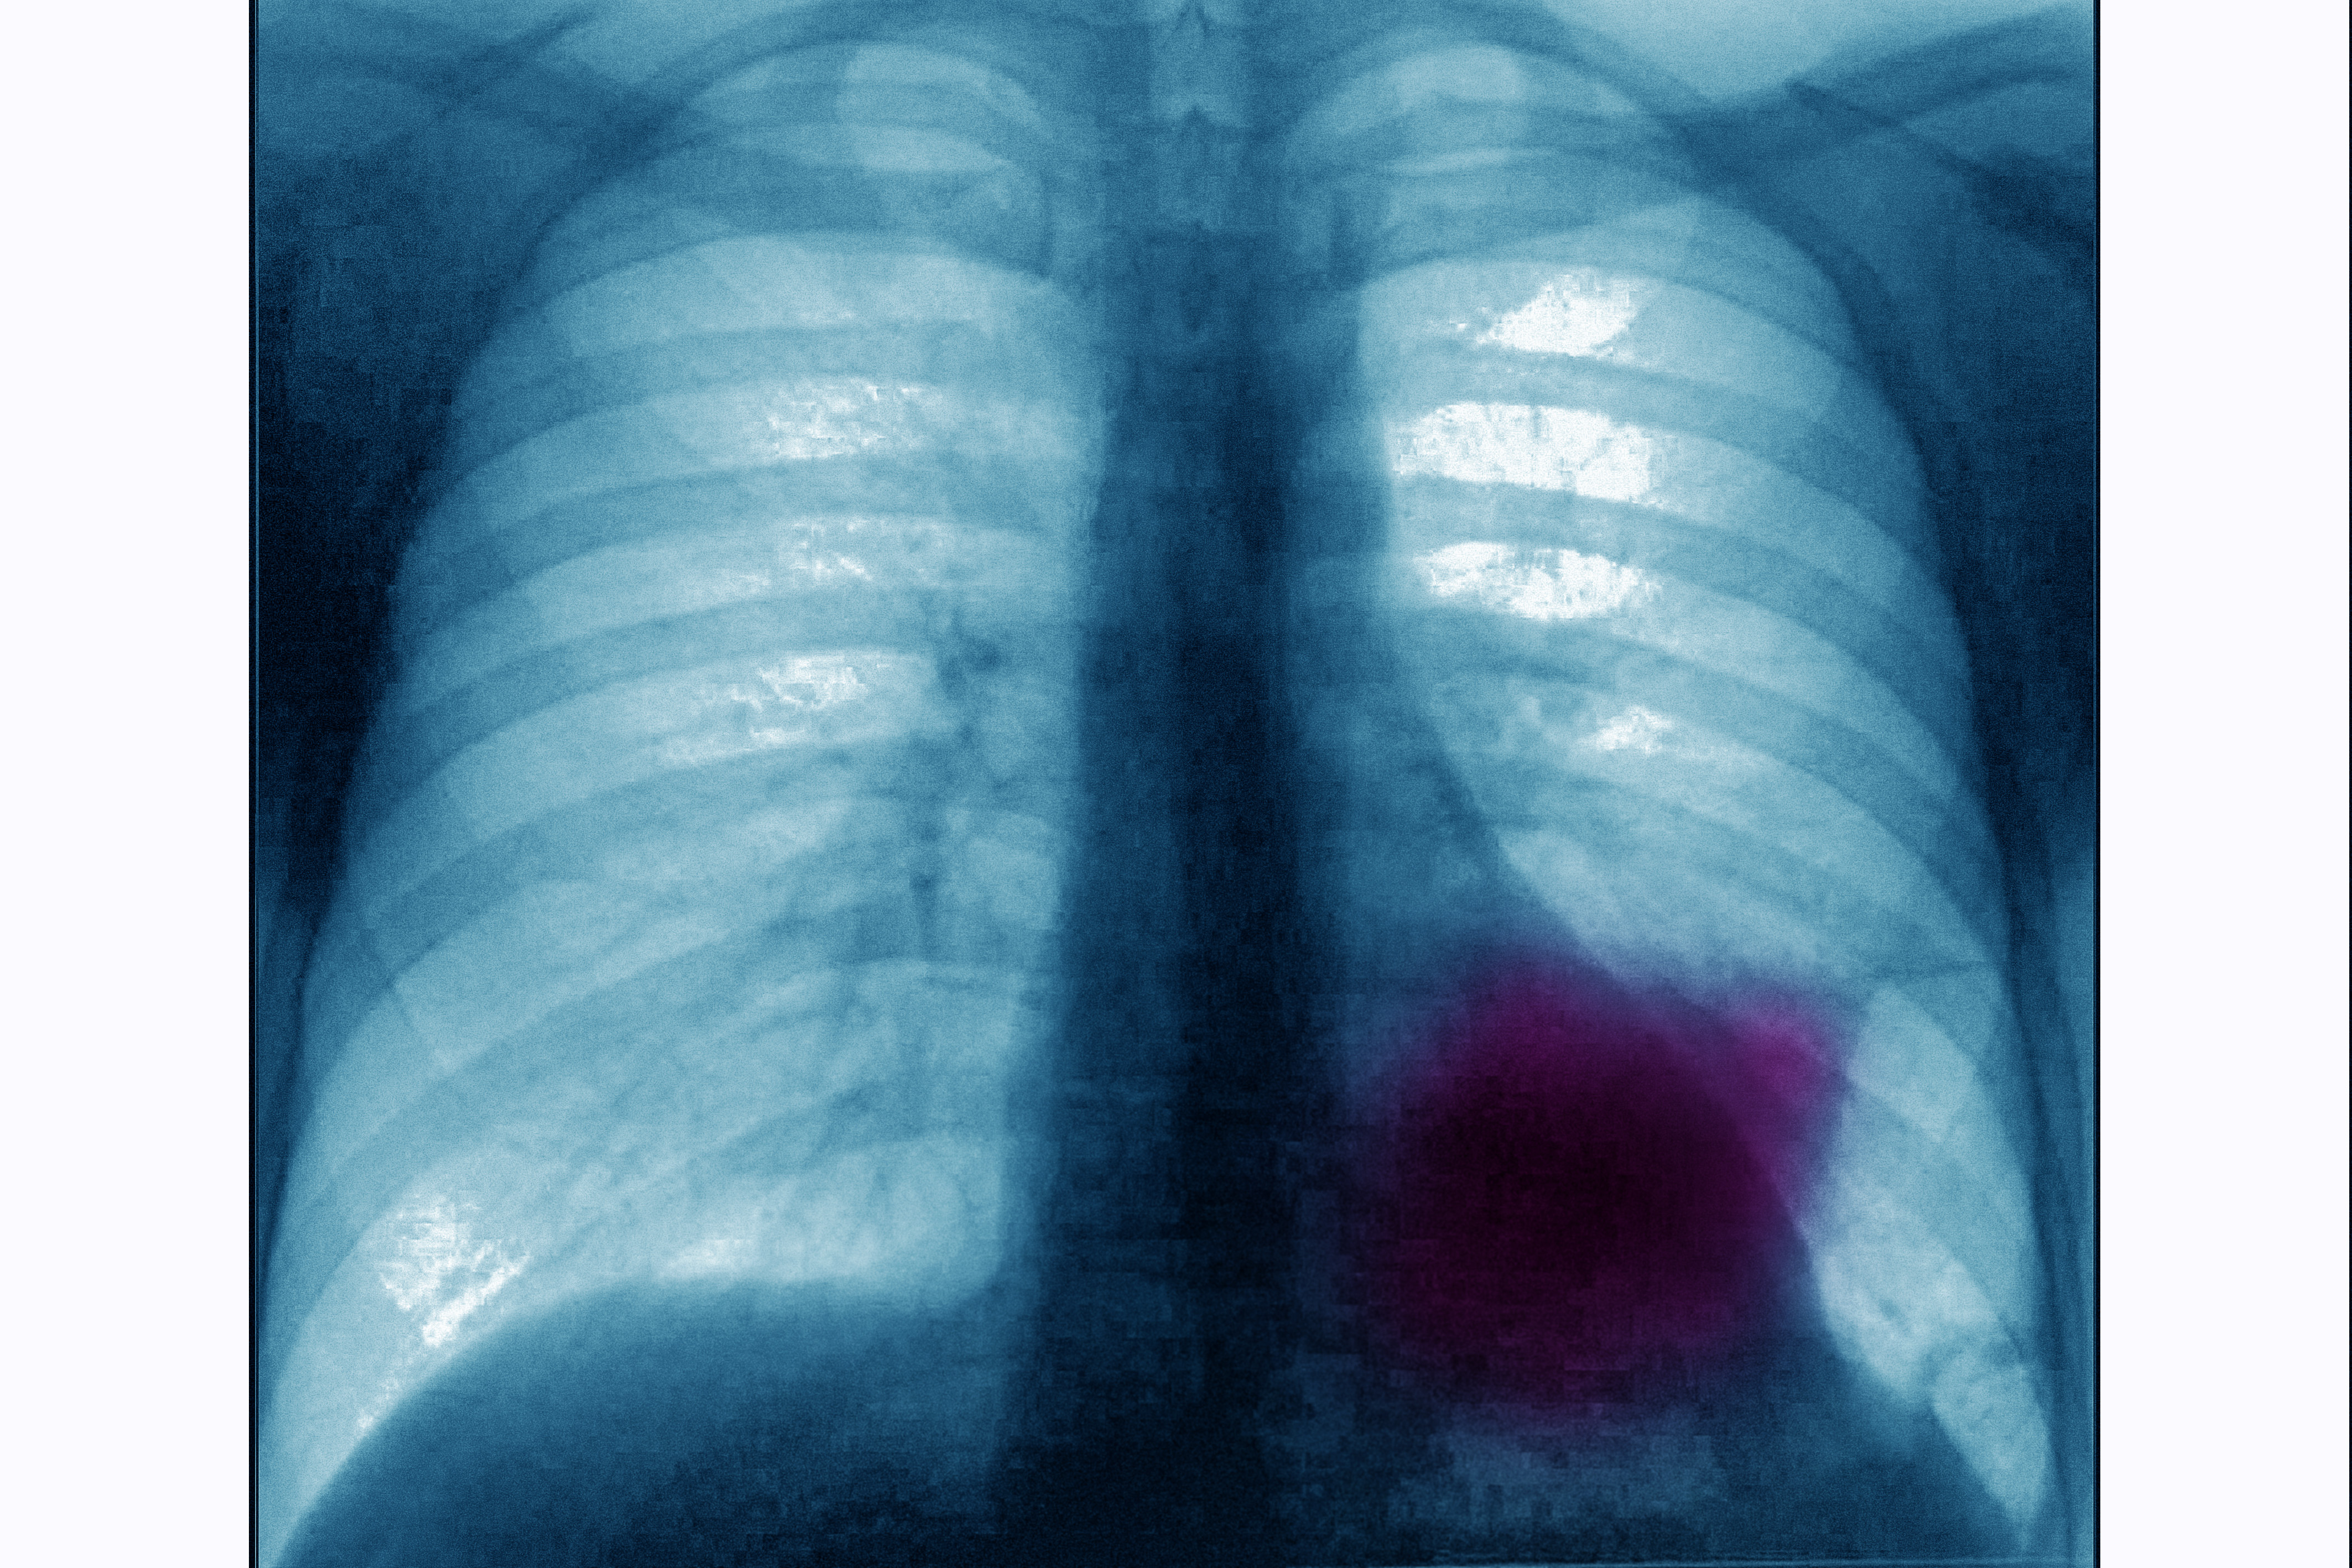

أصبح سرطان الرئة مصدر قلق خاص للنساء. وعلى الرغم من انخفاض وفيات سرطان الرئة بشكل مطرد في الرجال منذ عام 1990، إلا أنها استمرت في الارتفاع عند النساء، توجد هذه الفوارق بشكل رئيسي لأن النساء استمرين في التدخين في الستينيات والسبعينيات، عندما بدأ الرجال في الإقلاع. بالطبع هناك اسباب أخرى غير التدخين سنتحدث عنها في هذا المقال.

اعراض سرطان الرئة عند النساء

- لسرطان الرئة عدة أعراض. يتغير الصوت بسبب السعال وسعال الدم. ضيق في التنفس أو الصفير.

- 50 في المئة من الأشخاص الذين تم تشخيصهم بسرطان الرئة لديهم آلام في الصدر والكتف.

اسباب سرطان الرئة عند النساء

- يقتصر السرطان في البداية على الرئتين. قلة قليلة من المرضى يدركون أن الأعراض لا تظهر بسرعة،